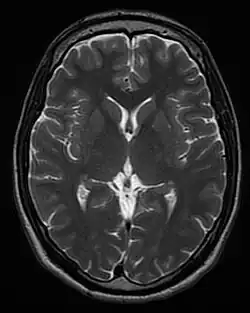

Diffusion weighted (DWI) Conventional DWI Measure of Brownian motion of water molecules.[17] High signal within minutes of cerebral infarction (pictured).[18]

Apparent diffusion coefficient ADC Reduced T2 weighting by taking multiple conventional DWI images with different DWI weighting, and the change corresponds to diffusion.[19] Low signal minutes after cerebral infarction (pictured).[20]